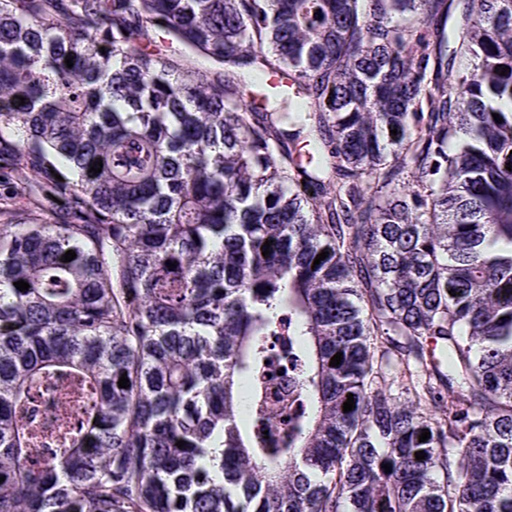

Refer to caption

Figure 3: Visualization of the segmented cells and the generated graphs from an arbitrary patch sample of GIST-PDL1. The four subgraphs from left to right are the raw patch image, the segmented cells masks, the patch image with overlaid segmentation masks, and the generated graph.

To better understand the learned graphs that are generated from histology images, Figures 3-8 investigate some random patch images from the three datasets and visualize the nuclei segmentation results and the associated graphs. In particular, the four subgraphs from left to right of each figure display the raw patch image, the segmented cells masks, the patch image with overlaid segmentation masks, and the generated graph.